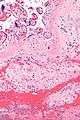

| Micrograph of a chronic deciduitis, showing the characteristic plasma cells. H&E stain. | |

Chronic deciduitis, also plasma cell deciduitis, is a type of long-lasting inflammation that arises in pregnancy and affects the endometrial stromal tissue (decidua).

It is associated with preterm labour.[1] The diagnosis rests primarily on the presence of plasma cells.[2]